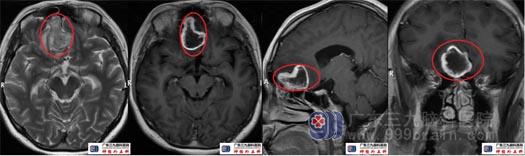

术前头颅MRI右侧额叶底部镰旁示一大小约37mm×25mm×30mm的团块状不均匀等长混杂T1、混杂等长T2异常信号影,Flair序列呈稍高、低混杂信号影,增强扫描后呈类环形强化,局部稍突入右侧筛窦内,周围示斑片状Flair序列高信号影。ADC图呈高、低混杂信号影。MRS示病变内可见明显升高的Lip峰,NAA及Cho、Cr峰均未见显示。提示右侧额叶底部镰旁病变,其内存在明显坏死,待排成人型弥漫性胶质瘤(或)不典型炎性肉芽肿病变。